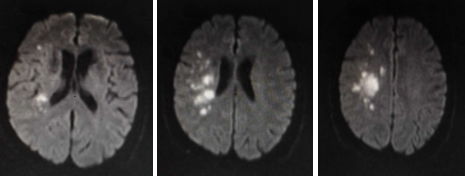

辅助检查:血常规、凝血功能、急诊生化均正常,免疫全项、甲功、血管炎抗体谱(-),心电图:正常窦性心律;心脏彩超:左室舒张功能稍减。头部MRI显示:右侧内分水岭区伴散在点状病灶。脑血管造影:右侧大脑中动脉(RMCA)狭窄、RMCA深穿支稀疏,右大脑半球的大部分由右大脑前动脉的软脑膜支反流供血。

图1. 入院急诊头部MRI